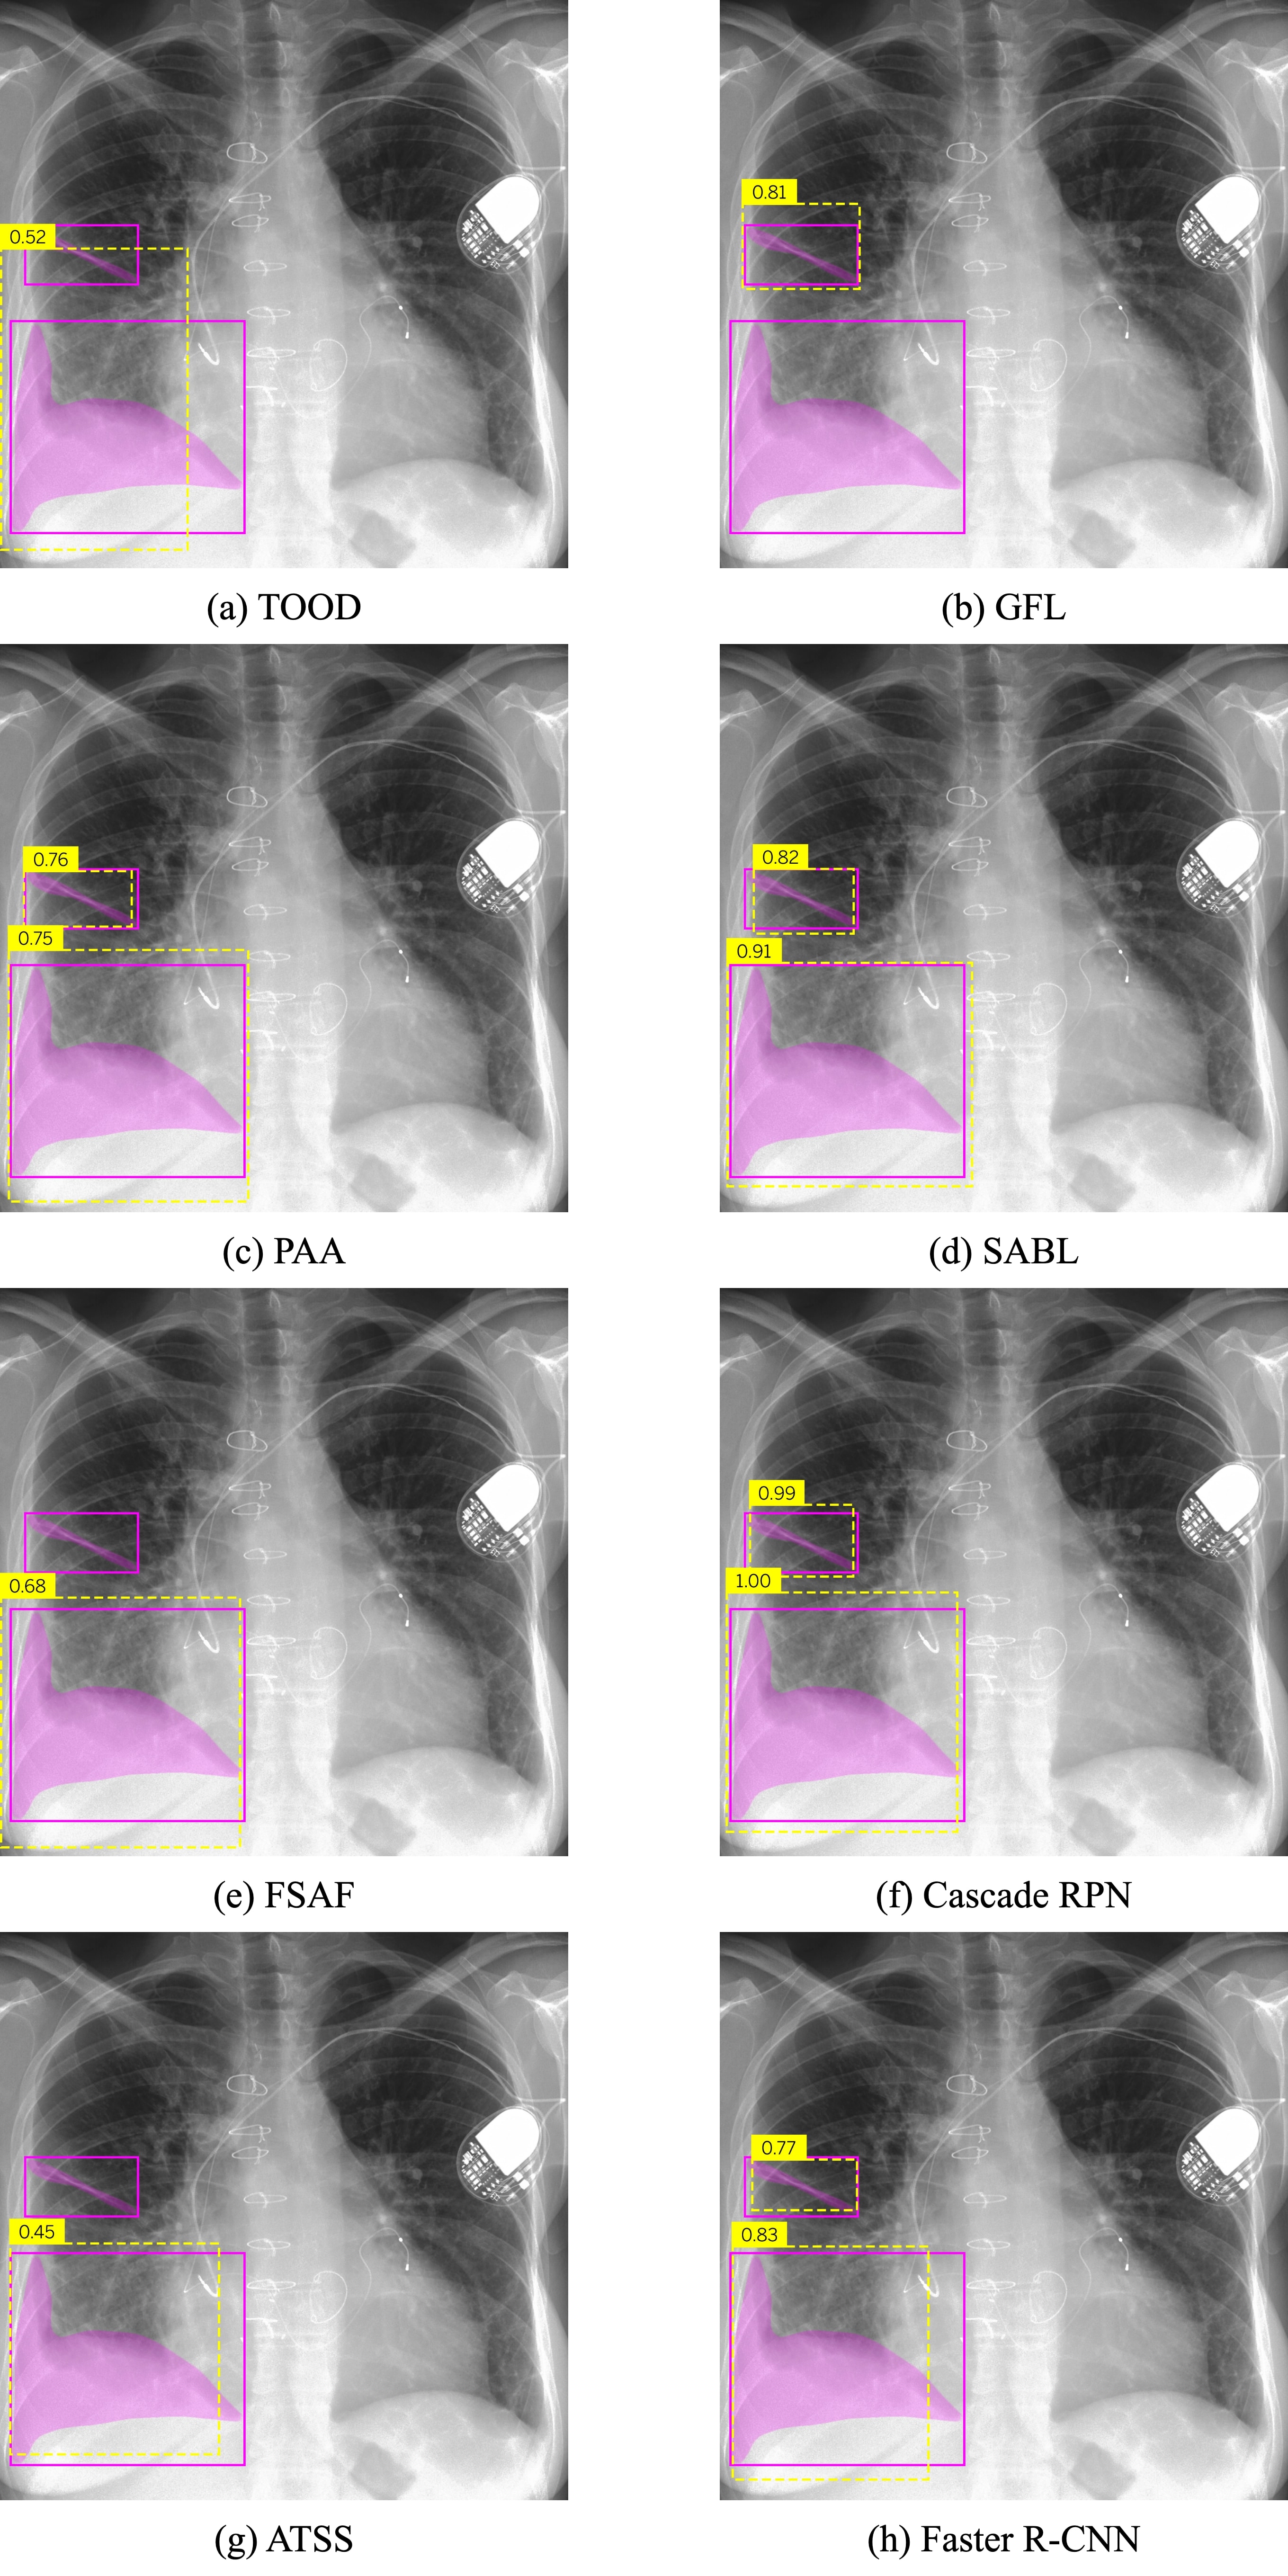

- Feature Detection: Eight object detection networks were trained to specialize in detecting individual features, including SABL, TOOD, Cascade RPN, PAA, Faster R-CNN, GFL, FSAF, and ATSS.

Visual assessment of network predictions for bat wings (Figure 4) and pleural effusion (Figure 5) demonstrates the model's capabilities across different radiographic features.